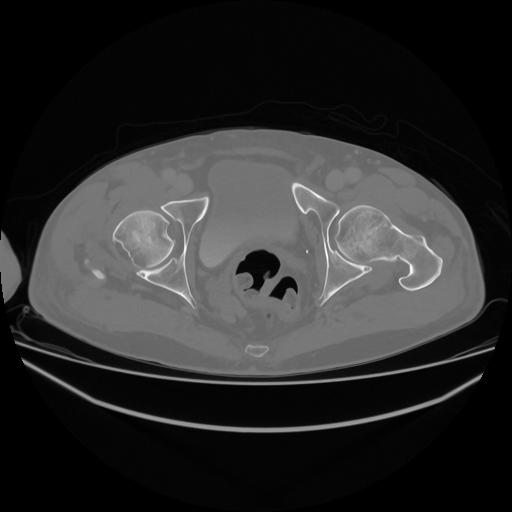

5 CUERPO,CE,Vol,1.0,CUERPO,,